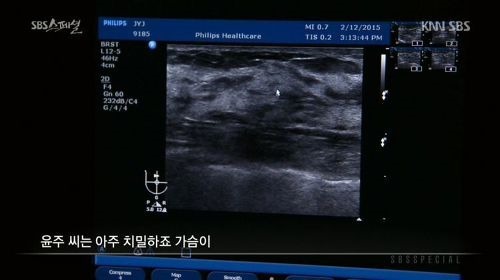

장윤주는 과거 SBS 교양프로그램 'SBS 스페셜-장윤주의 가슴 이야기'에서

"14살부터 가슴이 나오기 시작했다"며 "생각보다 크게 자랐다. 사이즈는 70에 C컵 정도 된다"고 털어놨다.

당시 방송에서 장윤주는 가슴을 초음파로 진단했습니다.

장윤주의 가슴 초음파 사진을 살펴본 의사는

"유선 조직이 가슴의 80%이상을 차지하고 있는 고도의 치밀유방이다. 지방 이식한 것도 안보인다. 보면 다 안다. (인공적인 것이)아무것도 없다. 자연산 맞다. 모유 잘 나오겠다"고 진단했습니다.

이에 장윤주는 "저의 가슴 수술논란을 확실히 풀었다"며 기뻐하며 "저도 꼭 모유수유하고 싶다"고 말했습니다.